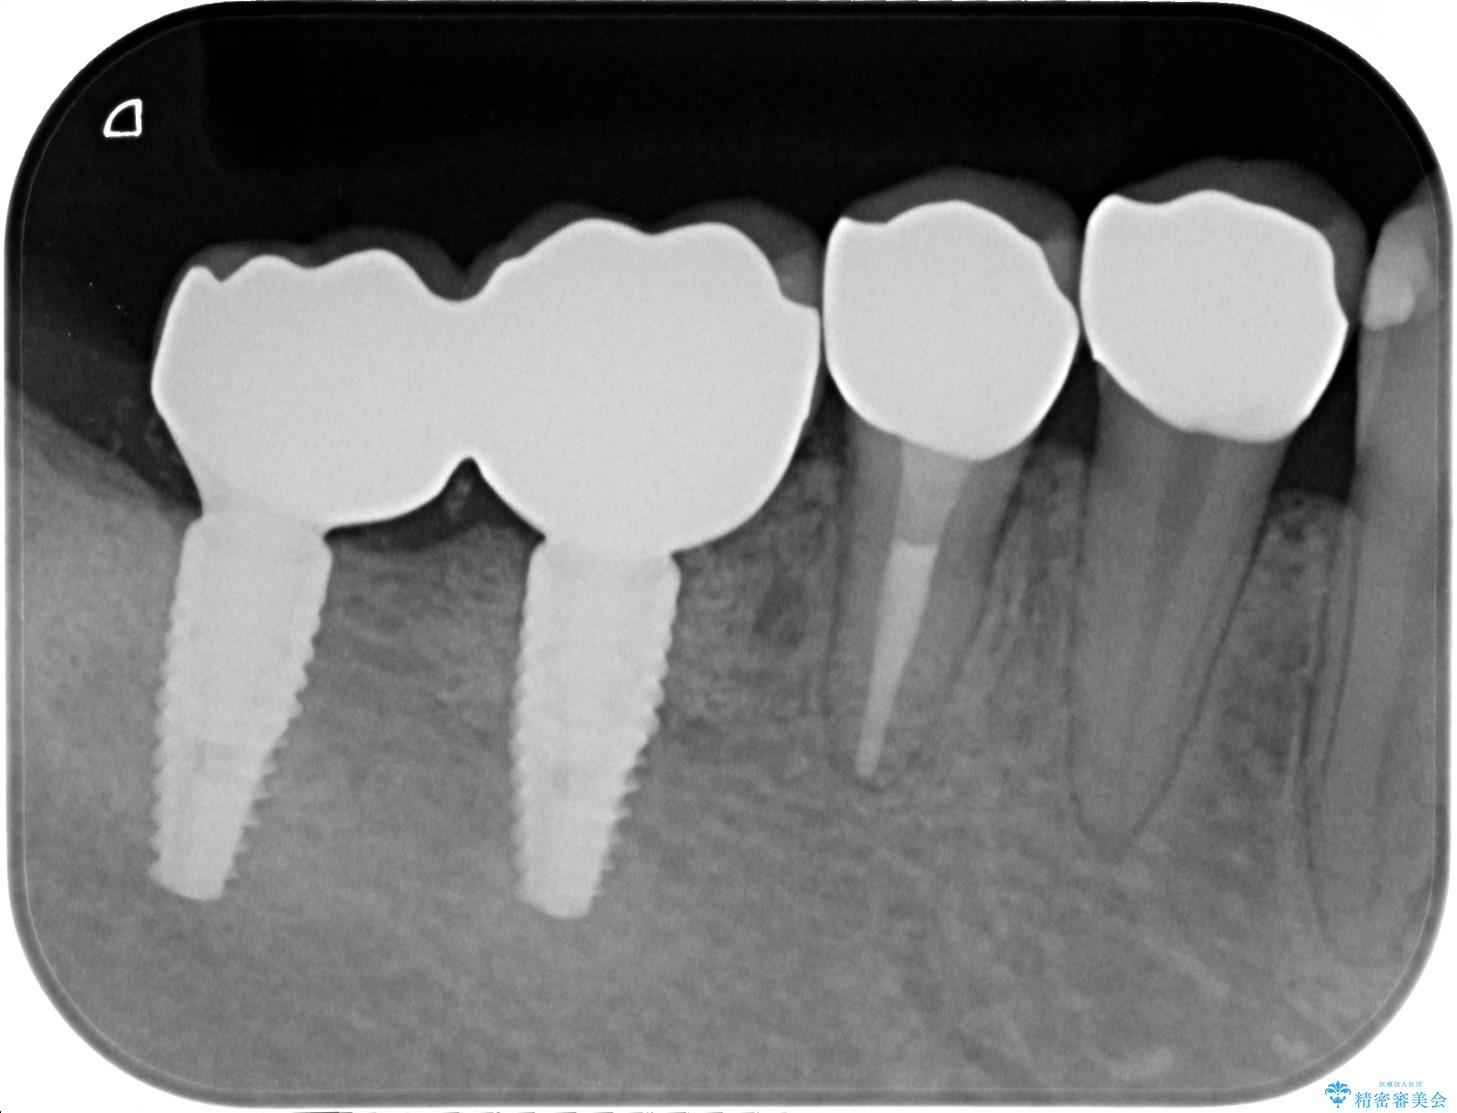

X線写真検査より、クラウンや銀歯の下で歯に大きな虫歯が発生し、抜歯を余儀なくされる状況でした。

虫歯に伴い歯槽骨の吸収も見られたので造骨後、インプラントを用いて咬合機能を回復します。